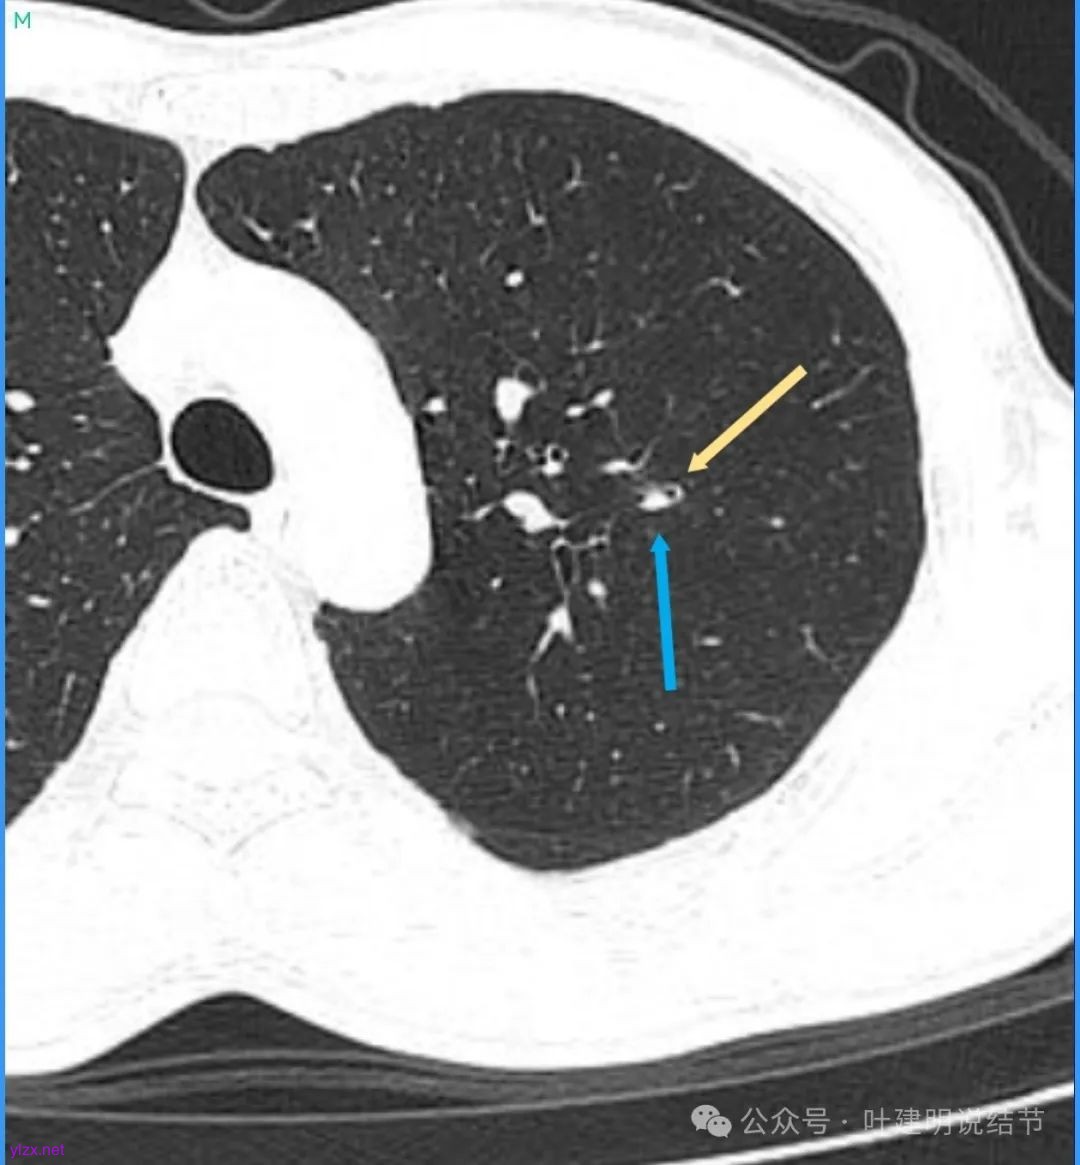

再看看近半年前2024年11月时的影像:

我们发现一是病灶与25年3月的几乎没有区别,二是原来蓝色箭头处不太像血管,而是结节边缘的一部分,而结节灶内又是有扩张支气管的。

左肺上叶这个病灶总体上来讲2025年3月的与2024年11月份相比没有显著进展。我们逐层从细节上去分析,会发现:1、病灶开始出现的层面就有临近的支气管扭曲变形,这些人用肿瘤导致的牵拉不能解释,反而用细支气管扩张伴慢性炎容易解释;2、病灶内部仍然多个层面都有见到扩张的细支气管,可是如果是肿瘤,与导致细支气管扩张相应的病灶本身的收缩力或者边缘毛刺又不明显;3、病灶边缘基本上都比较光滑平直,没有像外周浸润性生长的枫叶或者毛刺;4、虽然有血管贴边或者进入,但是说不上显著的血管异常增粗;5、整体来讲病灶实性成分密度过高,随访对比进展不明显,用结节是恶性不太能够解释相应的影像表现,所以我倾向于考虑是细支气管扩张伴有周围慢性炎或者肉芽肿性炎。至少从风险高低的角度来看,几个月的间隔没有明显进展的情况下加上位置又不好,如果手术需要切除范围比较多,所以应该在随访观察比较稳妥,可以考虑半年复查对比。意见供参考!